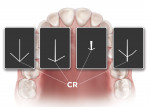

The impressions were then cut and separated (Figure 4) so as to prevent impingement of the trays with each other during the remainder of the procedure. When both impressions were completed, an intraoral tracing device was then plugged into the mandibular tray (Figure 5), similar to a Coble balancer, and the patient’s desired VDO was then determined by raising or lowering the pin (Figure 6). The Pala system includes tools to quantify the VDO before starting the case and then at any time until the end of record taking. Once the VDO was established and verified, and the number recorded, the patient then performed protrusive, retrusive, and lateral excursions, which are scribed by the VDO pin onto the maxillary tray pad.13 The lines drawn by the patient’s mandible represent the gothic arch tracing of the patient’s mandible with most recordings of these movements being either the shape of an arrow or one that resembles a chicken foot.14 The tip of the arrow, or the back of the chicken foot, represents the patient’s CR and was checked to determine if the patient could duplicate these movements (Figure 7). When this position could be reproduced to the clinician’s satisfaction, the trays were then locked in their respective position by using a fast-set bite registration material (Figure 8). The whole apparatus was then removed from the patient’s mouth, and the final measurement taken and recorded was the lip length from the premaxilla, using the other instrument provided. This measurement aids the designers in determining the amount of “show” of the maxillary incisors beyond the upper lip. These impressions and measurements represent all that was needed to fabricate the final dentures, which took an hour or less to record. The patient was dismissed and the case, along with the complete prescription, was sent to the laboratory.